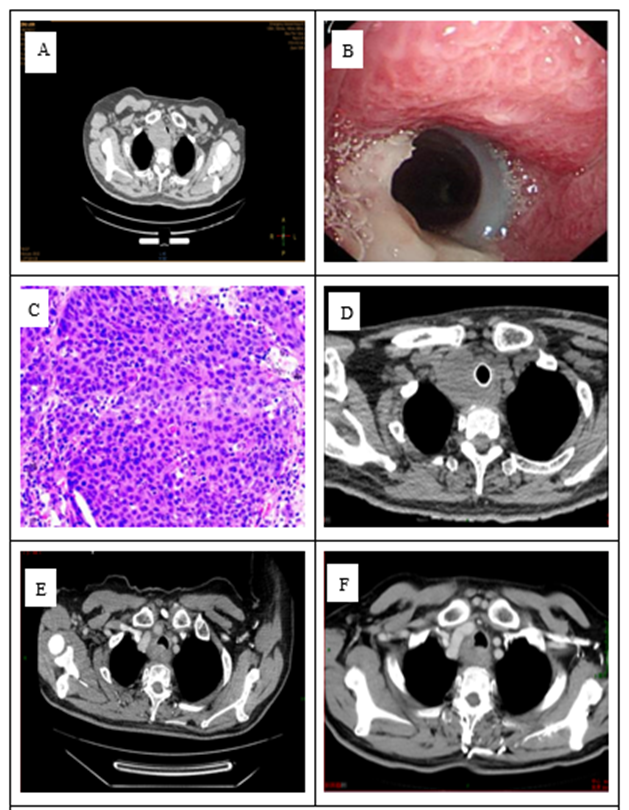

Case 2: A 67-year-old male patient presented with a "tracheal mass found on physical examination one month ago." He had a history of heavy smoking and drinking, with no history of cardiothoracic surgery or tuberculosis. Chest CT revealed an irregular mass behind the tracheal wall at the thoracic inlet, with a maximum cross-section of approximately 4.2 cm by 3.5 cm. The corresponding lumen was narrowed, with the lesion mostly protruding outward. The boundary with the adjacent esophagus and thyroid was unclear, and it was closely adjacent to the thoracic 1 vertebral body. The esophagus was compressed and narrowed. Esophagoscopy showed that the esophageal inlet, located about 16-18 cm from the incisors, exhibited an extrinsic compression bulge, causing narrowing at the esophageal entrance. Bronchoscopy revealed a local protuberance in the trachea, about 2 cm past the glottis, approximately 2 cm by 3 cm in size. The mass showed infiltrative growth with no distinct boundary and was locally accompanied by ulceration and erosion on the surface. Pathological examination confirmed poorly differentiated squamous cell carcinoma. Immunohistochemistry results were as follows: PD-L1 (22C3) (TPS = 50%; CPS = 50). The diagnosis was primary tracheal squamous cell carcinoma with mediastinal lymph node metastasis. The clinical stage was cT4N1M0, stage IV, as defined by the Bhattacharyya criteria. ECOG: 1 point. After surgical consultation, the tumor was deemed unresectable. In April-May 2024, the patient underwent two cycles of induction therapy with "Pembrolizumab + Liposomal Paclitaxel + Carboplatin," resulting in a reduction of the lesion. Chest volume rotational intensity-modulated radiation therapy was administered from June to July 2024, with the following prescription doses: 95% PGTV: 60.2 Gy/2.15 Gy/28 fractions, and 95% PTV: 50.4 Gy/1.8 Gy/28 fractions. Concurrent chemotherapy, consisting of Liposomal Paclitaxel + Carboplatin, was given during radiotherapy for two cycles. During treatment, Grade I anemia and Grade II radiation esophagitis occurred, which improved with symptomatic treatment. The patient is currently undergoing maintenance treatment with pembrolizumab. Follow-up until June 2025 showed no tumor progression for one year (Figure 2).

Figure 2: A: CT at diagnosis; B: Bronchoscopy findings; C: Esophagoscopy findings; D: Pathology HE × 200; E: CT after two cycles of induction; F: CT three months after radiotherapy completion.